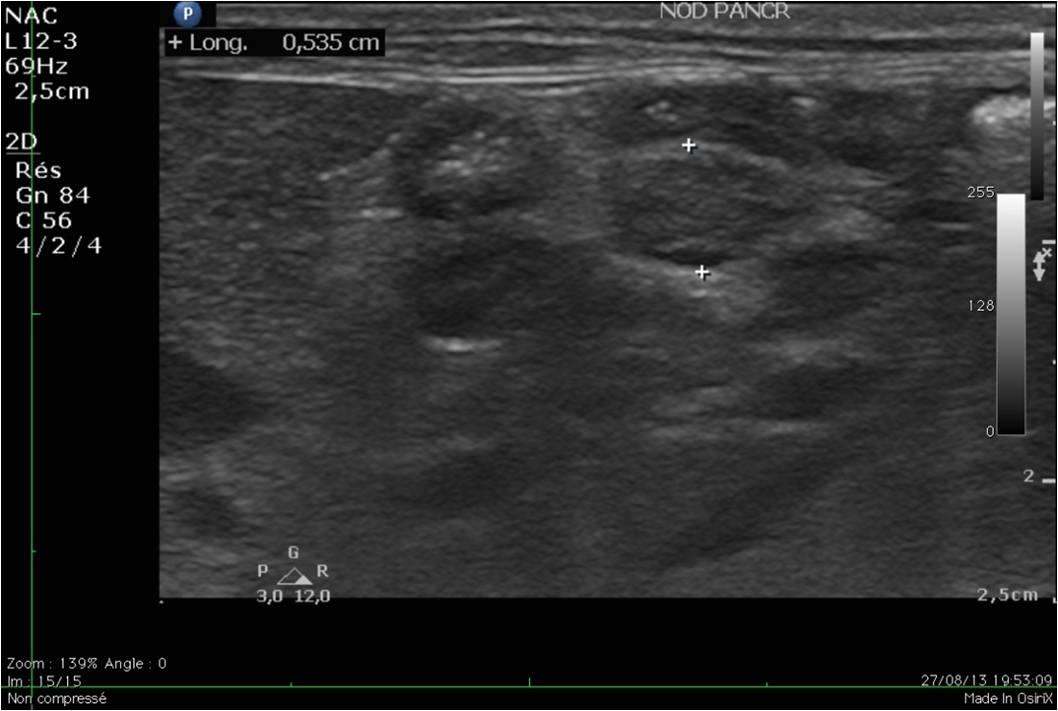

Les insulinomes sont des tumeurs du pancréas, le plus souvent bénignes. Elles sont particulièrement fréquentes chez les furets de plus de 5 ans. On retrouve les signes cliniques suivants: léthargie, augmentation du sommeil, paralysie des pattes arrières, bruxisme (grincements de dents), convulsions,... Il est actuellement suspecté que les furets consommant des croquettes riches en amidon seraient prédisposés à cette maladie.

Le diagnostic se fait par prise de sang et par échographie, réalisée par un vétérinaire expérimenté. Parfois, un traitement doit être administré en urgence, car les crises d'hypoglycémie peuvent être mortelles. Une hospitalisation est nécessaire en cas de crises convulsives. Les premières phases du traitement sont médicales mais une chirurgie (pancréatectomie) peut être recommandée dans certaines formes d'insulinome. Nous utilisons pour ce faire la technologie Ligasure pour minimiser le temps opératoire et les risques associés à l'opération.